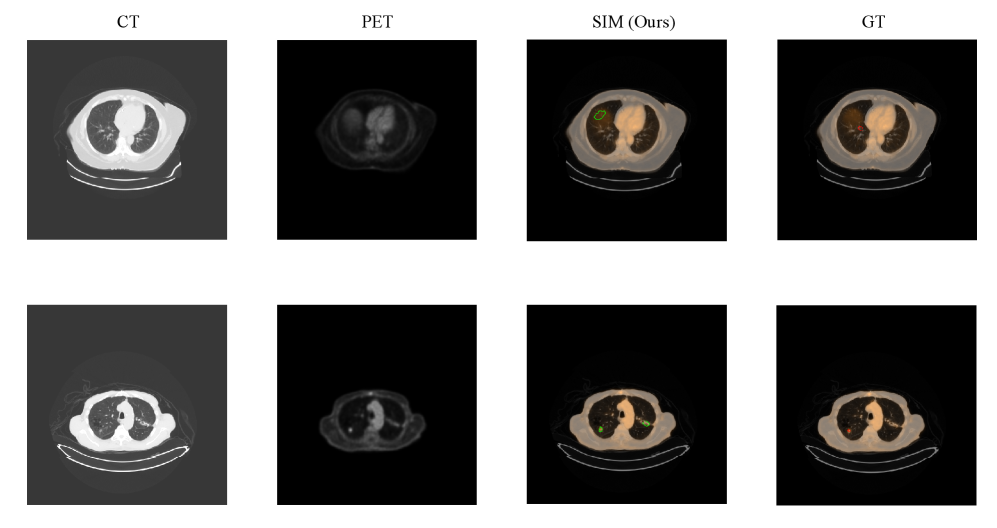

Refer to caption

Figure 4: Visual comparison of segmentation results from different models on representative PET/CT slices from the LUCID-PET/CT test set. Ground truth contours are shown in red, predicted segmentation in green. From left to right: input CT, input PET, ground truth, Baseline 2D, Baseline 2.5D, Finetuned 2.5D, Finetuned 2.5D + CBAM, Finetuned 2.5D + Non-Local Block, Finetuned 2.5D + SIM (Ours).

Figure 4 presents visual comparisons of segmentation results produced by different models. These examples are selected from the LUCID-PET/CT test set and demonstrate the influence of each module and training strategy on lesion delineation. The baseline 2D and 2.5D models without fine-tuning are easily affected by non-tumor signals and often fail to capture lesion boundaries accurately. In contrast, the finetuned models, especially the one incorporating the proposed SIM, achieve more precise and complete segmentation results. The selected samples include marginal slices, which typically have low PET signals, as well as slices that contain prominent organ signals that can mislead the models. Our method demonstrates robust performance under these challenging conditions and accurately delineates lesions.

The model also still struggles in highly challenging cases, such as those with low PET signal at the tumor boundary or with strong adjacent organ uptake. Figure 5 shows two representative failure cases: the model misses part of the lesion or produces false positives due to weak peripheral PET signals and interference from nearby organs. These results highlight areas for future improvement in multi-modal fusion and contextual modeling.

Figure 5: Representative failure cases. Left to right: input CT, input PET, model prediction, ground truth. The model misses tumor boundaries and includes false positives when PET signals are weak and adjacent organ uptake is high.